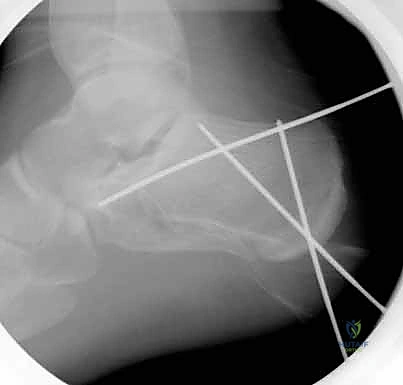

- التصوير بالأشعة السينية (X-rays): لأخذ فكرة أولية عن الكسر (زوايا بوهلر وجيسان - Bohler’s and Gissane’s angles).

4. التثبيت المؤقت

يتم استخدام أسلاك معدنية دقيقة لتثبيت الشظايا في مكانها مؤقتاً، ثم يتم التحقق من دقة الرد باستخدام جهاز الأشعة السينية داخل غرفة العمليات (C-arm) لضمان عدم وجود أي انزياح ولو بمليمتر واحد.